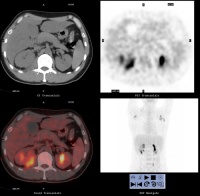

四。对于较大的瘤体,行CT增强、扫描瘤体强化,有助于胆囊癌的诊断。